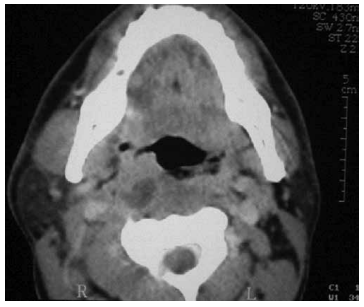

Paciente adulto, sexo masculino, procura o pronto-socorro devido à febre (39 ºC), dor de garganta, dificuldade para engolir e dor cervical há 3 dias. Foi realizado o exame a seguir.

A conduta nesta situação clínica é a